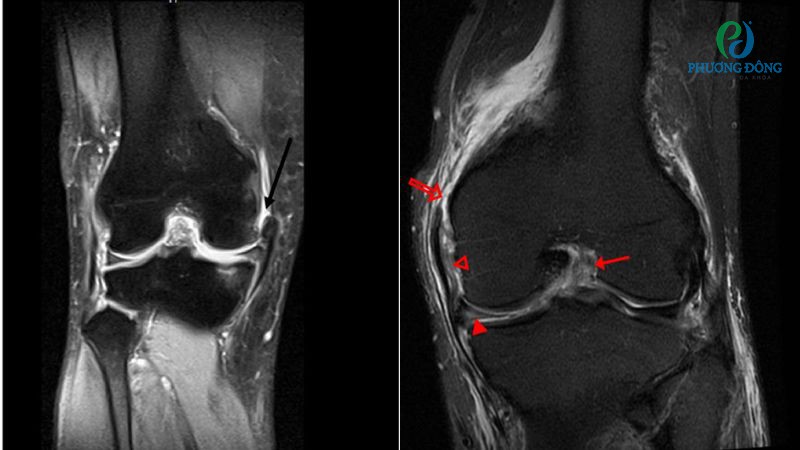

Chẩn đoán chấn thương dây chằng bên trong gối (MCL)

Phần lớn các chấn thương dây chằng bên trong gối được xác định thông qua việc thăm khám lâm sàng. Bác sĩ tiến hành bài kiểm tra đơn giản, bằng cách gập nhẹ đầu gối và tác động lực lên vùng khớp để kiểm tra độ vững.

Trong trường hợp đầu gối bị lỏng lẻo, hoạt động không còn ổn định có thể gợi ý dây chằng MCL bị tổn thương. Tuy nhiên để xác định cụ thể mức độ rách, phát hiện tổn thương kèm theo trong khớp gối, bệnh nhân cần thực hiện thêm các xét nghiệm hình ảnh như:

- Chụp MRI đánh giá mức độ tổn thương dây chằng, phát hiện các tổn thương phần mềm khác như sụn chêm, dây chằng chéo.

- Siêu âm xác định mức độ rách của dây chằng bên trong gối, kiểm tra vùng mô mềm quanh khớp có bị tổn thương hay không.

- Chụp X-quang đầu gối nhằm loại trừ khả năng gãy xương, một số tổn thương xương khác kèm theo dây chằng.

Phương pháp chẩn đoán mức độ chấn thương dây chằng bên trong đầu gối